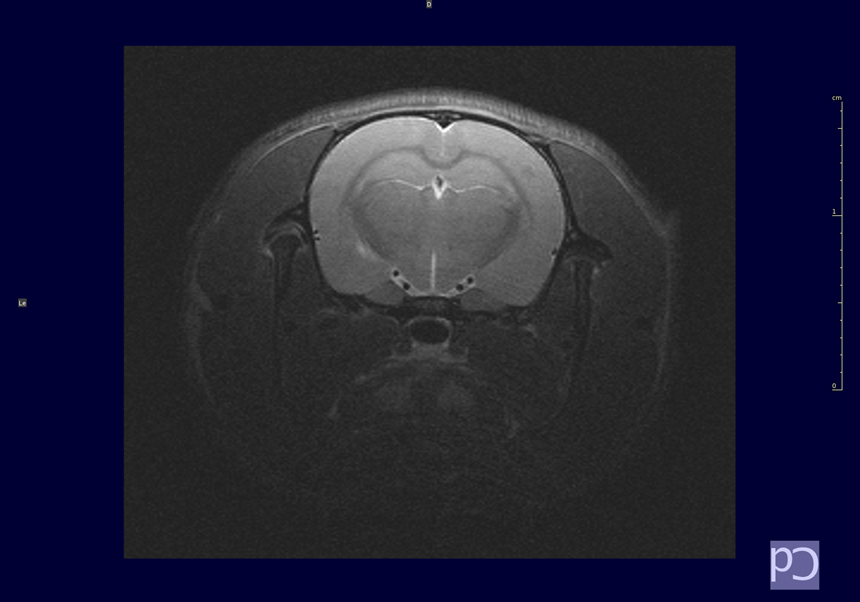

Amb aquest equip podem obtenir imatges potenciades en T1, T2 i densitat protònica, espectroscòpia localitzada, angiografies, difusió, …

Imatges: